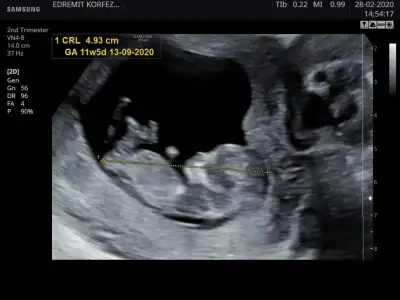

M mely15 bi bakarmısın canım ben tahmin ettim arkadaşa sen ne diyorsun 12+4 usgKızlar kızlarvideodan ekran görüntüsü aldığım 2 fotoğrafta nub birinde paralel birinde dik duruyor hareket ettiği sırada değişiyor olabilir mi

bilemedim sizede ekleyim istedim yakaladığım kısımları ❤ M mely15

Ikra meyra Eki Görüntüle 2601535 Eki Görüntüle 2601536

Kız gibi gibi diyorum net değil usg başka varsa paylaşın emin olamadım12+4 günlük yorumlayabilir misiniz![]()

Sanki kız gibi ama emin değilim nubu karanlık kalmış 12 yada 13 haftada paylaşın emin olmak istiyorum![]()